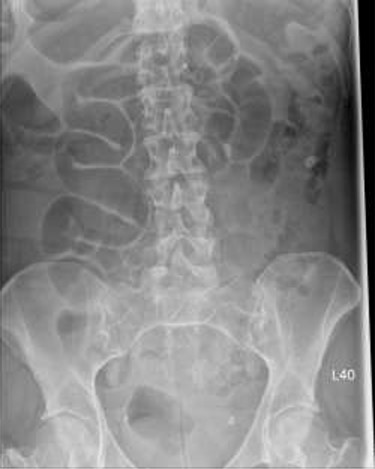

Patient initially diagnosed as biliary colic and surgical team had been contacted. Plain Abdominal radiograph showed dilated small bowels loops (Fig. 1). Chest radiograph revealed air under right hemi-diaphragm (Fig. 2). CT scan was done in emergency department and confirmed interposition of bowel between the diaphragm and the liver with a vascular/mesenteric pedicle swirl suggestive of malrotation or volvulus of the right colon. There was marked mural thickening and bold dilatation with high attenuation mucosa in keeping with closed loop obstruction and possible necrosis (Figs 3 and 4).

CT scan shows interposition of ileum, cecum and ascending colon between liver and diaphragm pushing right loop of the liver and gallbladder medially.